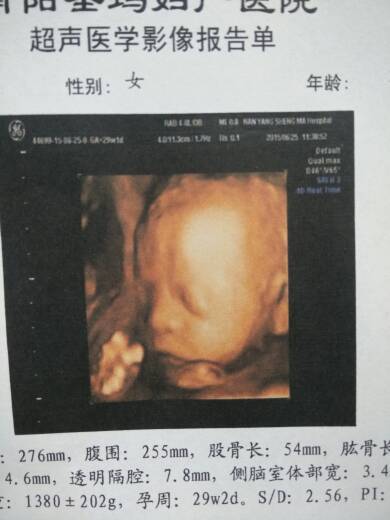

我29周的四维看的清楚吗?不是兔唇把吧! 我29周的四维看的清楚吗?不是兔唇把吧! 点击展开 且行且珍惜~ 2015-06-25 14:54 为您推荐: 其他回答 我31周去照的 承诺,以化泡沫! 2015-06-25 21:36 不是的ii 幸运在身边(^з^)-☆ 2015-06-25 19:28 问问医生、好可爱的宝宝 轩轩,我爱你 2015-06-25 16:56 不用担心,有问题医生会告知的 期待宝妹 2015-06-25 16:33 四维不是6个月就得做吗 我们★在路上ξ 2015-06-25 16:33 加载更多 相关问题 四维彩超是不是可以看宝宝兔唇?哪里照的最清楚? 怀孕29周,请问我的这些四维数据还算正常吗 29周可以做四维码吗